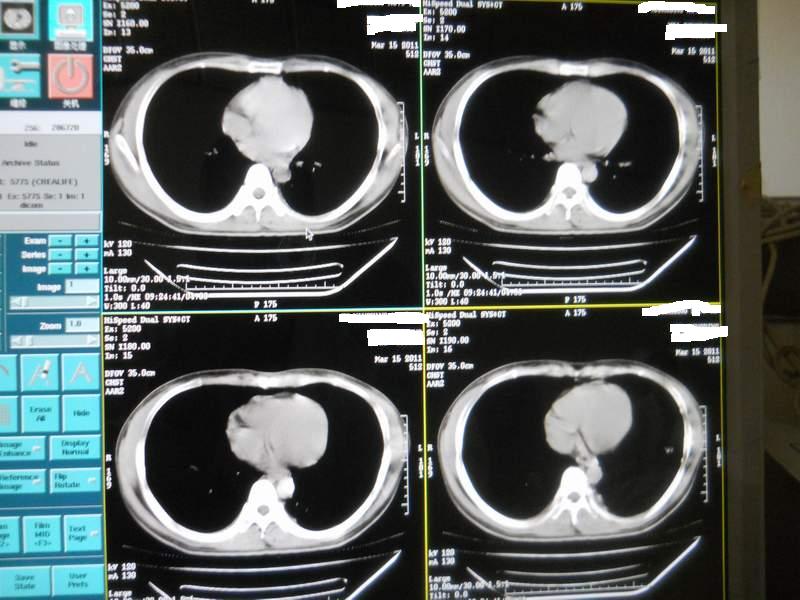

肺霉菌感染

男,22岁,一年前诊断马尔菲尼青霉菌感染,多次复查CT。多次HIV阴性。最近两次CT图片。有实验室结果。

最近实验室检查结果:霉菌感染。